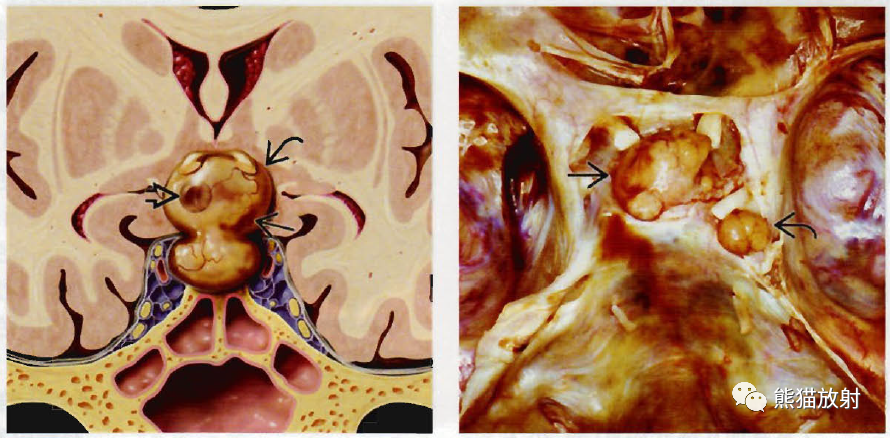

(左)冠状位图显示“雪人样”或“8字形”鞍区/鞍上肿块(弯箭)。病灶内有小的出血灶(空箭)和囊变(直箭),垂体与肿块不可区分;事实上,腺体即肿块。

(右)大体病理显示大腺瘤通过鞍膈向上延伸进人鞍上池(箭),向侧方生长进人海绵窦(弯箭),图像中去除了部分海绵窦顶壁。